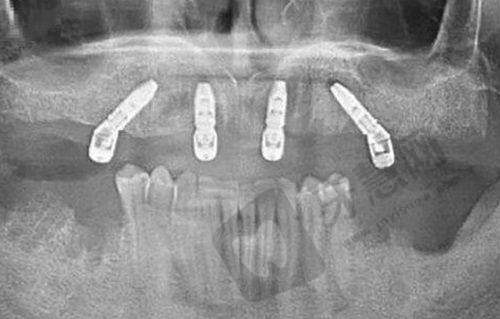

复杂咬合重建患者:凭借 38 年正畸经验,通过 3D 扫描数据分析,提出针对性联合方案,解决复杂口腔问题。

特色项目优势:门诊部主打颞下颌关节、牙齿矫正以及种植牙专科项目,在颞下颌关节病理性口腔问题治疗上有专精技术和丰富经验。